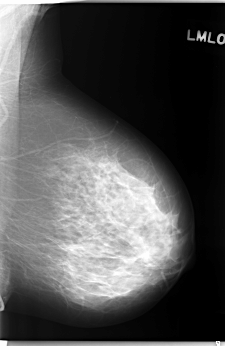

C_0243_1.LEFT_MLO

LEFT_MLO LINES 5880 PIXELS_PER_LINE 3816 BITS_PER_PIXEL 12 RESOLUTION 50 NON_OVERLAY